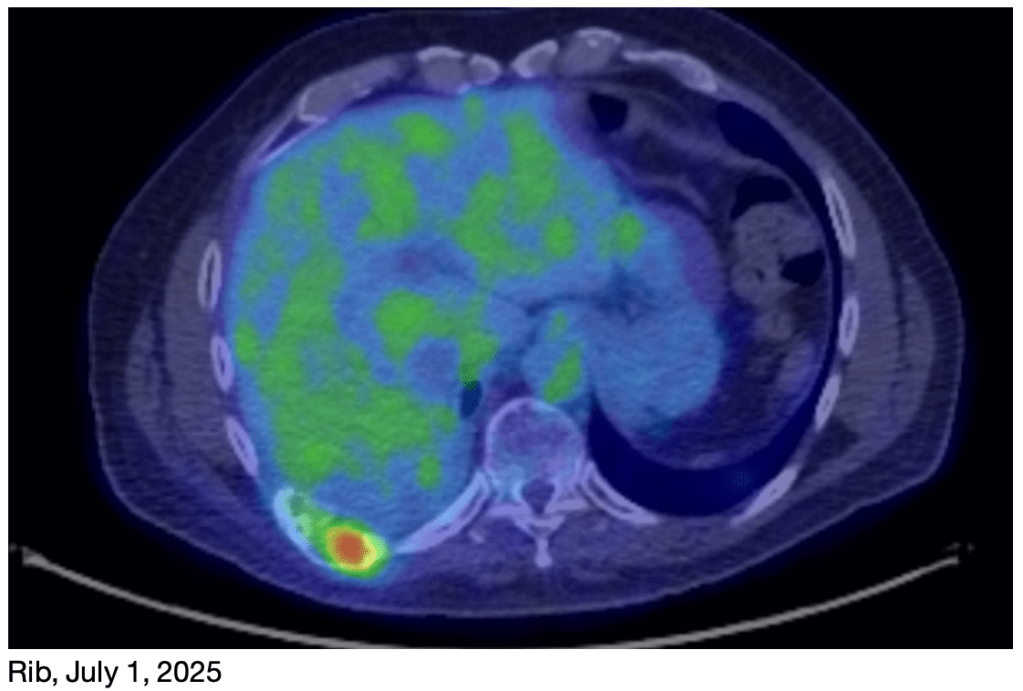

I have some sobering news. I had a PET scan on Tuesday and it appears that the rib tumor is trying to make a comeback. My original treatment plan had just 4 rounds of chemo, and then immunotherapy after that. While the chemotherapy worked well, it appears that the immunotherapy has not been as effective as was hoped.

As you can see in the images, the rib tumor was basically absent in the March 30th image, but has reappeared in the image from this week (July 1st).

We met with my oncologist this morning. Since the chemo was effective last Fall, and the tumor is now much smaller than it was back then, he is very hopeful that it will be effective again. While we will do another Next Generation Sequencing test to determine the genetics of the tumor, he expects that it will not have changed significantly since the first time. So the same chemo treatment should still be effective. Tentatively, we plan 6 rounds this time, instead of the 4 we had before. We will likely start next Thursday.